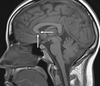

1

Q

A

quadrigeminal cistern